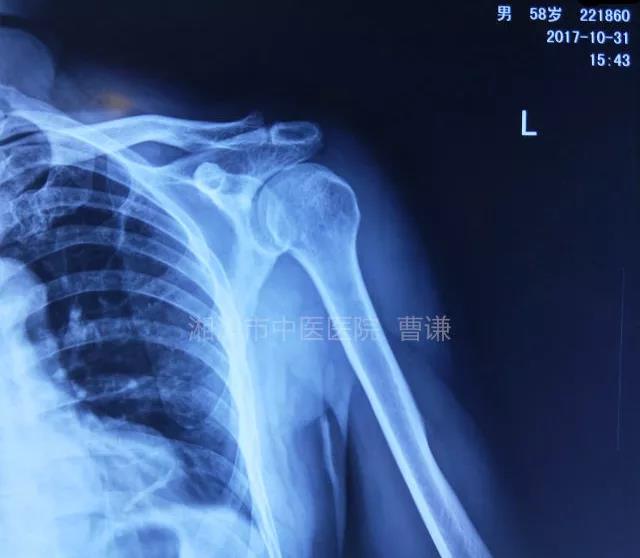

就诊我院后完善CT,诊断明确——左肩关节后脱位:

予以手法复位后拍片复查显示“灯泡征”消失,复位成功。讨论:肩关节后脱位在临床较为少见,特别是影像科经验不足很容易漏报,所以我们临床医生一定要自己仔细阅片,同时要结合体查来进行诊断,防止漏诊。肩关节后脱位时体查也有明显特征:肩关节前方明显变平,喙突较平时明显凸起容易触及,而肩关节后方明显丰满,上臂一般处于内旋内收位,无法主动外旋外展。肩关节后脱位的手法复位相对于前脱位的复位来说也比较容易。患者一般可以取坐位,助手自患侧腋下环抱患者稳定患者躯体,术者一手拉患肢上臂稍牵引内旋,一手自后方推顶肱骨头一般可以复位,如果单纯推顶无法复位也可以术者两手握住伤肢缓慢外展并沿肱骨纵轴牵引,然后逐渐外旋上臂即可复位。整复完成后可以把持患肢作肩关节各个方向的小幅度被动活动,防止肩关节粘连,肩关节后脱位的固定方法与肩关节前脱位的固定方法不同,应将患肢置于上臂外展、后伸、外旋位固定,即外展30度、后伸30度和轻度外旋位,用外展支架固定3周后,循序渐进开始肩关节功能康复。